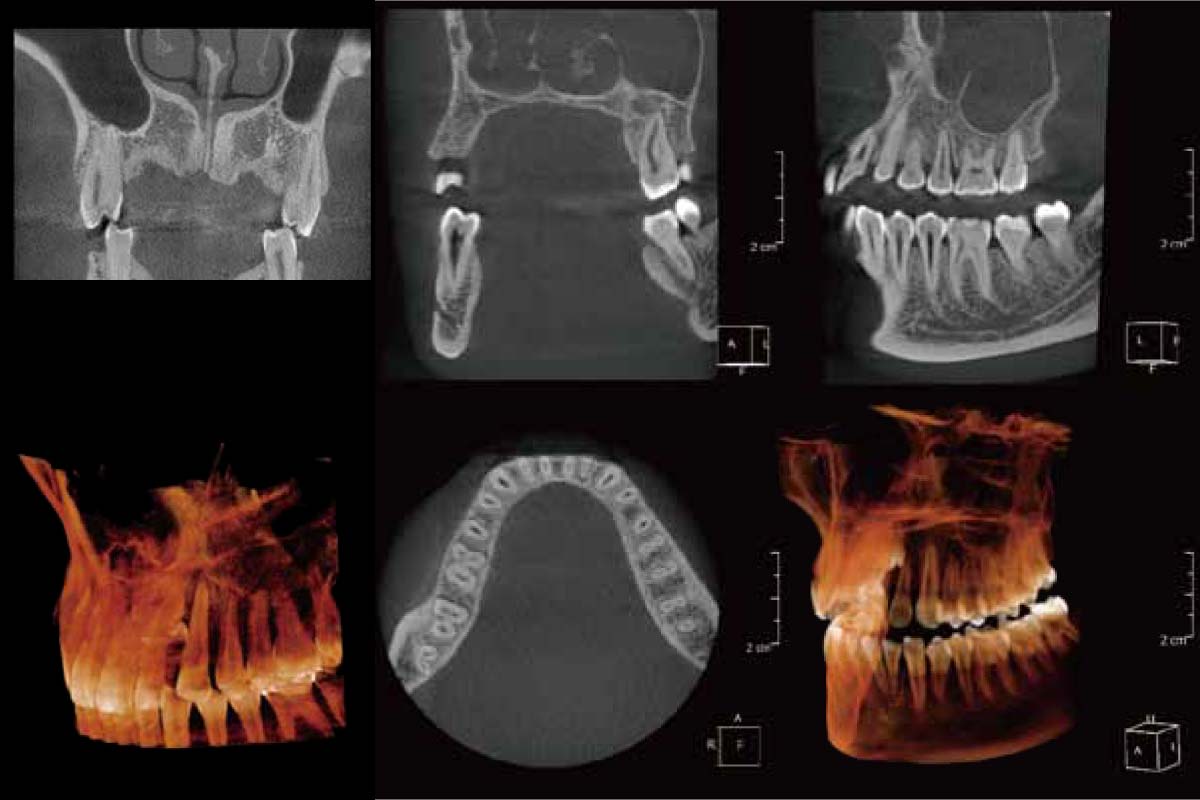

精密な診断をするために、まずCTを撮影いたします。インプラントを入れる位置の確認や種類など事前に治療をシミュレーションすることができるからです。シミュレーションの結果はご説明の際にモニターでご確認いただけます。